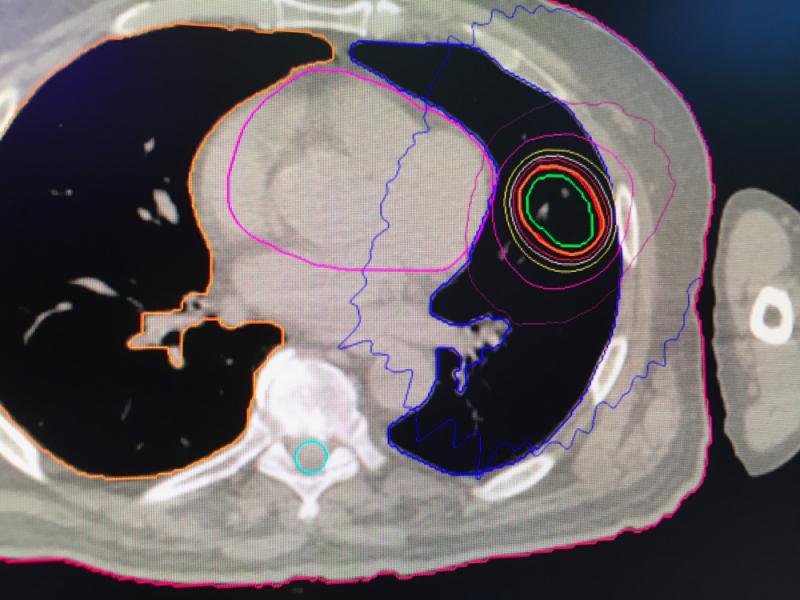

Below are photos from the American Society for Radiation Oncology (ASTRO) 2019 meeting September 2019 in Chicago. The annual conference has about 12,000 attendees. It is a showcase of the latest advances in radiation oncology technologies. Below are images of some of these radiation therapy technologies from the ASTRO expo floor with captions explaining them.